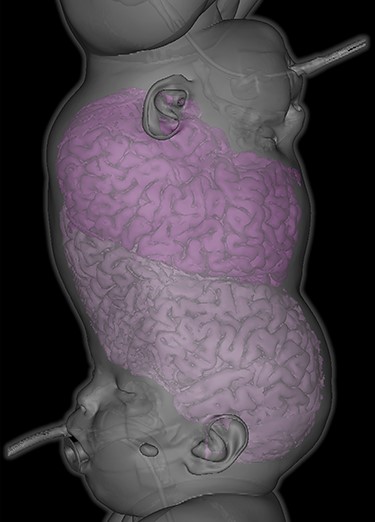

Lagophthalmos appreciated in right eye of both twins under general anaesthesia. Twin 1 (left) displayed right lagophthalmos of 3 mm whereas Twin 2 (right) displayed right lagophthalmos of 6 mm.

In the first of four staged surgical separation procedures, we performed tissue expansion to permit separation and craniofacial reconstruction (Fig. 2). During this procedure, full anterior and posterior segment examination was achieved under general anesthesia. Examination findings for Twin 1 included right lagophthalmos of 3 mm (Fig. 3) due to abnormally high brow position causing right corneal punctate epithelial erosions, visualized using the Keeler Portable Slitlamp (Keeler Ltd, Windsor, UK). Anterior segment examination was otherwise normal. Indirect ophthalmoscopy revealed normal macular reflexes and healthy optic discs with cup-disc ratios of 0.3. Twin 2 had the same findings as Twin 1, except right brow was comparatively higher, causing 6 mm lagophthalmos (Fig. 3) and exposure keratopathy in the form of more widespread punctate epithelial erosions. Both were treated with chloramphenicol 1% eye ointment QDS and sodium hyaluronate 0.2% eye drops Q2H, to both eyes, resulting in clear corneas within 2 weeks.